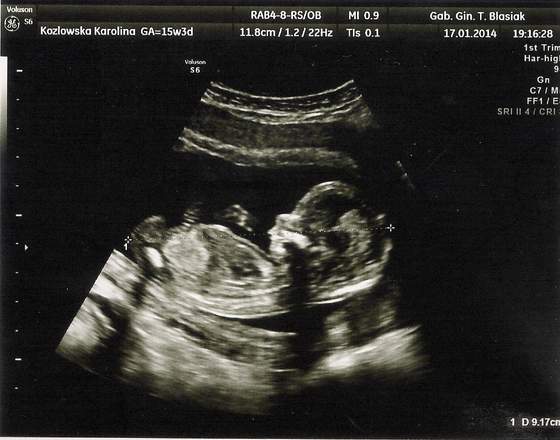

wizyty dzień do nocy, tamten na NFZ nic nie mierzył, tylko CRL a ten? Wszystkie kości pomierzył, paluszki policzył, główkę zmierzył, nawet mózg i móżdzek, serduszko dokładnie obejrzał ile komór, jak krew wpływa do serca, jak wypływa, posłuchaliśmy serduszka jak bije, czy budowa pępowiny jest ok, czy kręgosłup jest ok, jejku tyle rzeczy że aż nie mogłam się nadziwić, dostaliśmy chyba z 10 zdjęć z USG, i całą stronę A4 z opisami co badał, jakie są wyniki i czy jest ok. Najfajniejszy moment był jak przełączył na widok 3D i w tym samym czasie Maleństwo zakryło twarz raczkami tak jak małe dzieci się zakrywają i udają, że ich nie ma

niesamowite to było, aż wszyscy się zaczęliśmy śmiać :-)

oto kilka zdjęć naszej (chyba) córeczki